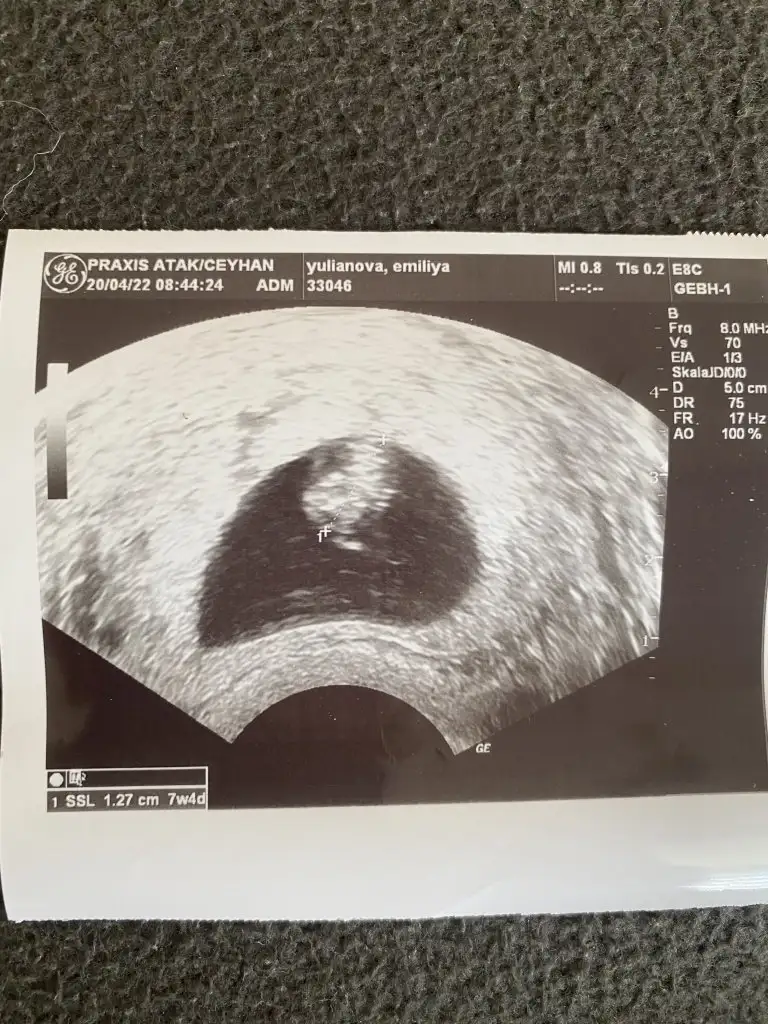

Banada bakarmisiniz vajinal ultrason 7 hafta 4 gunluk

Eklentiler